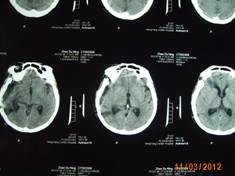

近日,一名來自常寧的58歲女性患者,因右側(cè)肢體麻木,頭暈3月入住衡陽市中心醫(yī)院神經(jīng)外科。頭顱增強磁共振檢查明確右側(cè)中顱窩底巨大腦膜瘤,約10*6*5cm3大小。經(jīng)過嚴密的術(shù)前檢查和全科術(shù)前討論,以科室主任鐘三寶主任醫(yī)師為首的手術(shù)組經(jīng)過4個小時的顯微鏡下手術(shù),順利的全切腫瘤。因腫瘤巨大,瘤體切除后局部留下一很大空腔,容易并發(fā)腦組織移位、腦出血,導(dǎo)致嚴重并發(fā)癥。術(shù)者創(chuàng)新地使用了水囊,逐步減壓等方法,使患者平穩(wěn)地度過了腦組織復(fù)位關(guān)。術(shù)后未出現(xiàn)任何并發(fā)癥,恢復(fù)良好,順利出院。

(術(shù)后復(fù)查患者恢復(fù)順利)